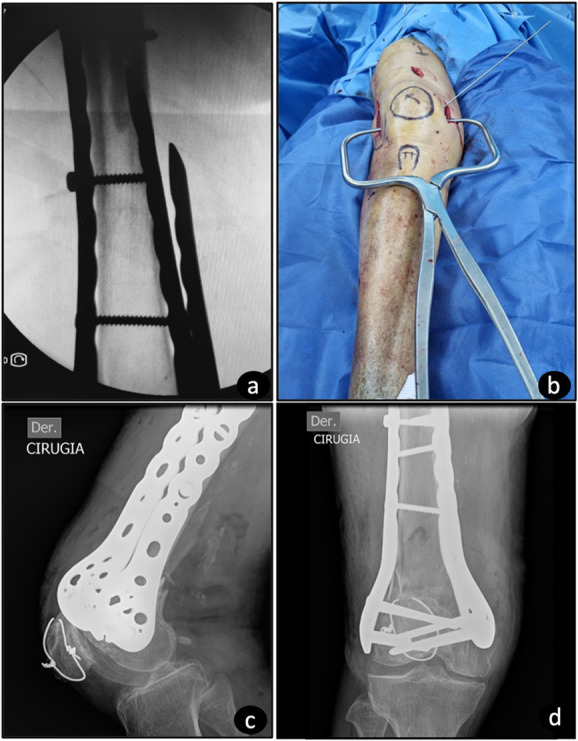

Introduction: Lateral locking plates are commonly employed for the fixation of distal femur fractures. However, scenarios involving medial comminution, extremely distal fractures, periprosthetic fractures, or nonunion could necessitate medial augmentation. This study explores the possibility of using lateral distal femoral locking plate systems for medial fixation by employing the contralateral plate.

Methods: This study presents a technical note on the application of lateral distal femur locking systems for medial augmentation in patients as indicated by current literature findings. Postoperative imaging modalities, including radiography and computed tomography (CT), were used to assess the plates' fit to the distal femur. Three cases following the specified technical note are presented.

Results: The various plate systems, all comprising distal femur locking systems, demonstrated adaptability to the medial femur anatomy as confirmed by intraoperative visualization and postoperative radiographs, including two-dimensional and three-dimensional CT scans. It has also been possible to achieve at least 3 independent fixation points regardless of the size of the medial condyle.

Conclusions: Locking distal femoral plates can be a viable option for medial augmentation in indicated cases, achieving anatomical adaptation to the distal femur. This provides robust augmentation without the need for additional instruments beyond those used for the lateral cortex.